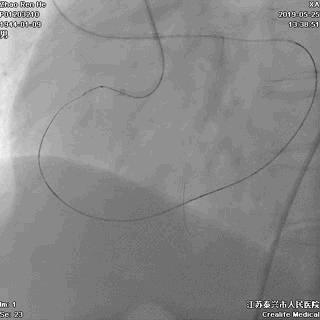

逆向途径开通RCA